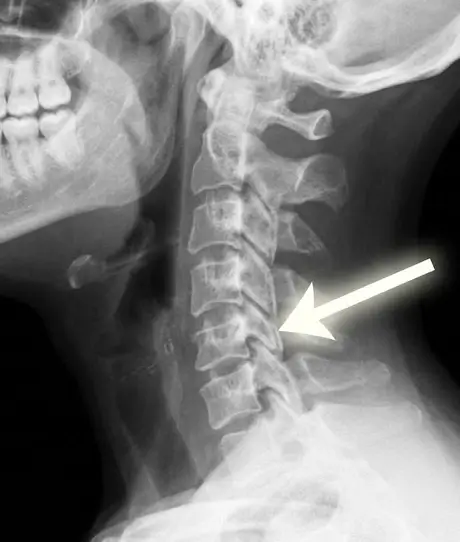

Using MRI, X-ray, and neurological evaluation, he identifies the source of neck pain and develops personalized treatment plans. Options include physical therapy, injections, and minimally invasive procedures for patients in Beverly Hills and the Greater Los Angeles area.

Neck pain often originates from the cervical spine structures, including cervical discs, facet joints, spinal nerves, ligaments, and muscles. Common causes include:

• Cervical herniated disc – disc material pressing on a cervical nerve.

• Cervical degenerative disc disease – age-related disc wear and tear.

• Cervical stenosis – narrowing of the spinal canal compressing the spinal cord or nerves.

• Trauma or injury – whiplash or direct impact to the cervical spine.